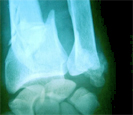

![]() |

Knochenbruch am Unterarm |

Bei Knochenbrüchen, die aufgrund von Knochenmetastasen auftreten, spricht man auch von pathologischen Frakturen.

Diese Frakturen treten nämlich, da der Knochen durch die Metastasen geschwächt ist, bereits nach Ereignissen auf, denen ein gesunder Knochen standhalten würde.